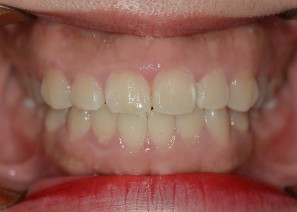

Before

After